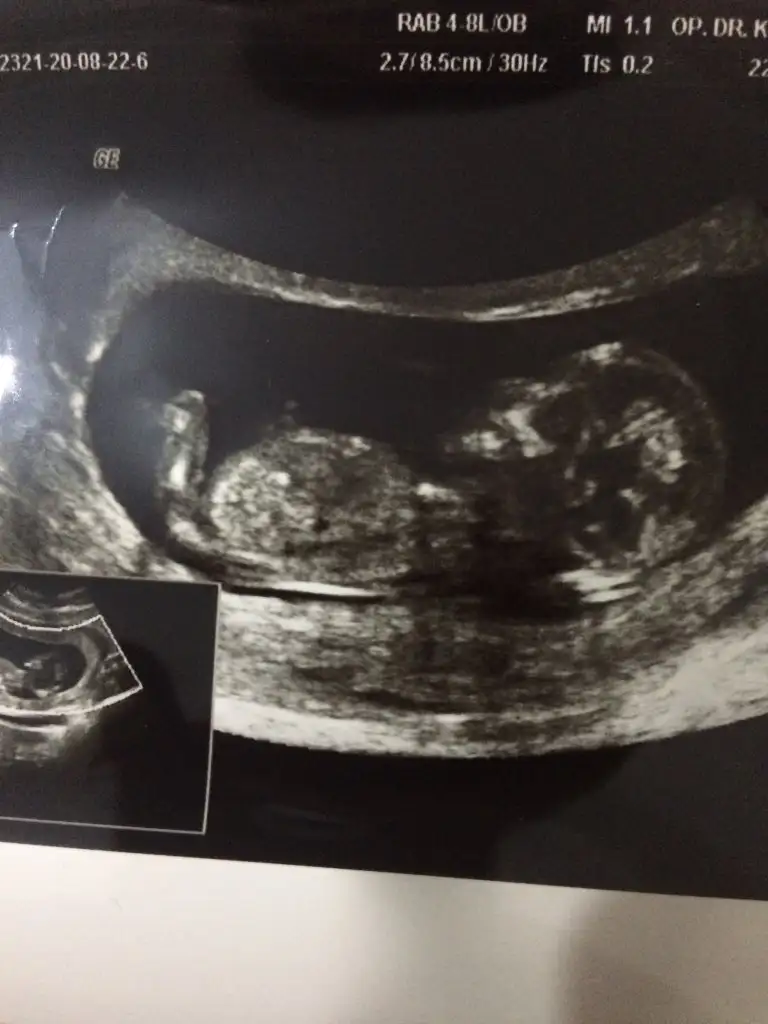

Banada tahmin yürütün

• 78B3FD87-3824-48F6-BD06-424FCEB5E299.webp

78B3FD87-3824-48F6-BD06-424FCEB5E299.webp

27 KB · Görüntüleme: 119